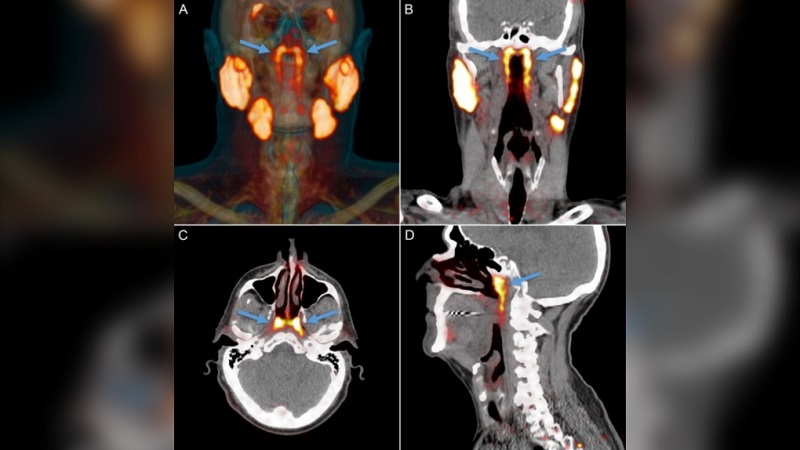

Cặp tuyến nước bọt lớn này ẩn sâu ở nơi giao nhau giữa khoang mũi và cổ họng. Ảnh: Viện Ung thư Hà Lan

Trong lúc xem xét các bức ảnh quét từ một thiết bị giúp hình dung các mô một cách chi tiết, những nhà nghiên cứu nhận thấy hai cấu trúc lạ thường nằm ở trung tâm đầu: một cặp tuyến phẳng, hình gai, dài vài inch, nằm trên các ống nối từ tai đến cổ họng.

Bối rối trước những gì vừa trông thấy, họ đã tiến hành giải phẫu hai tử thi và phát hiện ra rằng các tuyến này có đặc điểm tương tự với những tuyến nước bọt đã biết nằm dưới lưỡi. Các tuyến mới cũng được nối với các ống dẫn lưu lớn – một dấu hiệu cho thấy chúng đang vận chuyển chất lỏng từ nơi này sang nơi khác.

Dù chưa thể lý giải hết được vì sao trước đây các nhà giải phẫu học không biết đến sự tồn tại của chúng, nhưng rõ ràng “chúng nằm ở một vị trí khó tiếp cận, và phải cần những thiết bị chụp rất nhạy để phát hiện ra chúng,” TS Wouter Vogel, nhà ung thư học bức xạ tại Viện Ung thư Hà Lan và là tác giả của nghiên cứu cho biết. Các tuyến nước bọt lớn khác của cơ thể nằm gần bề mặt da hơn, trong khi đó cấu trúc thứ tư này lại nằm dưới đáy hộp sọ.